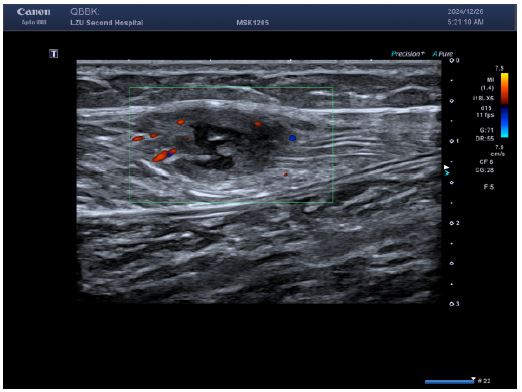

Figure 2: Color Doppler flow imaging showed a small amount of short rod-shaped blood flow around the lesion.

Lower limb ultrasound: Detected a hypoechoic lesion within the intermuscular space of the right calf. Initial impression: Schwannoma suspected; CEUS recommended.

The reasons for the misdiagnosis of this patient as a benign tumor were as follows: (1) The initial diagnostic context involved routine ultrasound without documented extramuscular malignancy, precluding sufficient justification for metastatic suspicion; (2) Sonomorphological mimicry manifested as well-circumscribed, spindle-shaped anechoic foci with smooth margins, distinct hyperechoic capsules, and posterior acoustic enhancement within the calf musculature—features pathognomonic for schwannoma yet discordant with the infiltrative borders characteristic of aggressive malignancies; (3) Vascular analysis (Figure B) revealed sparse punctate vascular signals rather than the abundant internal/peripheral flow or large perforating vessels typical of subcutaneous cancers; (4) CEUS kinetics further reinforced misdiagnosis through arterial-phase peripheral hyper-enhancement with central non-enhancing zones, maintained circumscribed margins, and early washout in adjacent tissues—collectively aligning with classical benign enhancement profiles and creating a compelling illusion of non-malignant pathology.